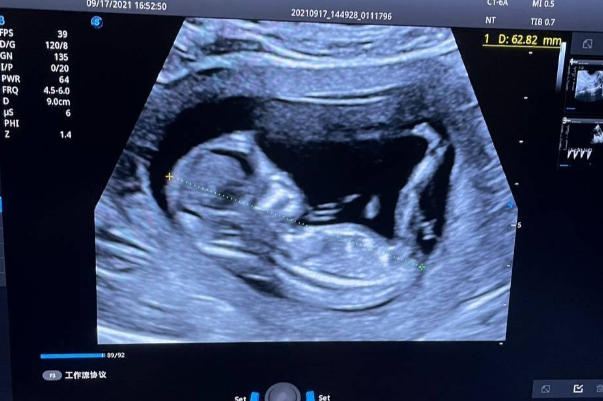

NT(Nuchal Translucency)即胎儿颈项透明层厚度检查,是孕早期通过B超测量胎儿颈后部皮下液体积聚厚度的专项检测。这项检查通常在妊娠11至13周+6天进行,因该阶段胎儿淋巴系统未发育完善,颈部液体积聚现象最易观测。其核心筛查目标为评估胎儿患染色体异常(如唐氏综合征)及先天性心脏病的风险,当NT值≥2.5毫米时,提示需进一步诊断。

检查前孕妇需提前预约并保持膀胱适度充盈,检查时采用经腹部或经阴道超声探头扫描。专业医师会多角度测量胎儿顶臀长确认孕周,并在胎儿自然姿势下选取正中矢状切面进行三次NT值测量取最大值。整个过程无创无痛,约需20-30分钟完成。需特别注意的是,NT检查需严格把控孕周窗口期,过早可能无法显影,过晚则因淋巴系统发育导致液体吸收而影响结果准确性。